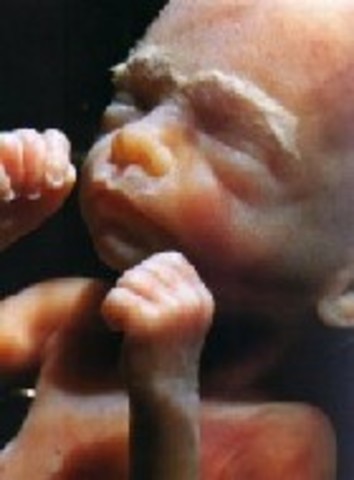

• Week 9 of the Firts Trimester

Week 9 of the Firts Trimester

In this week the Embryo now has control of its wrist and elbows, also now gaining the ability to swim around in a fluid filled sac.

Facts:

1)The embryo has grown to measure 30 mm (1.2 inches) in length.

2)The Embryo's see through skin allows you to see its veins.